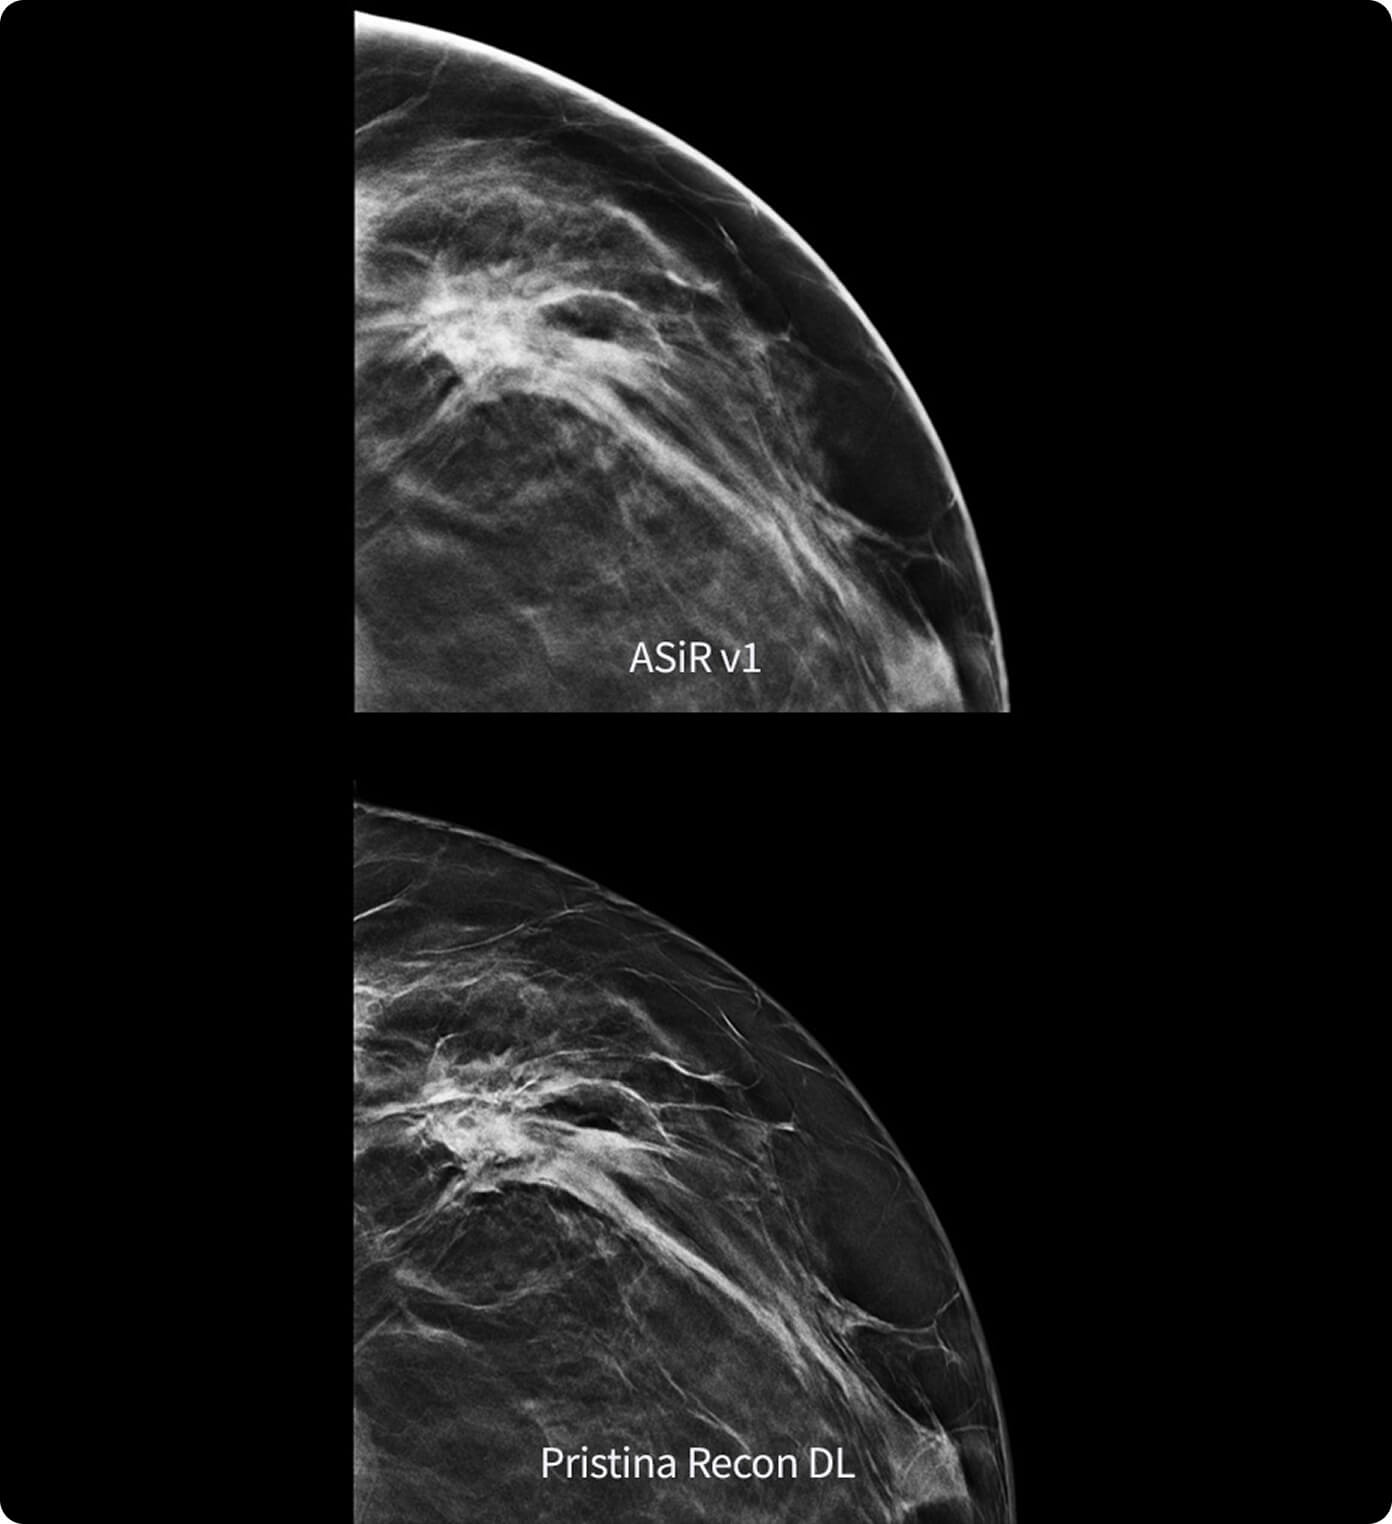

AI-based decision support: Breast Assistant and Thyroid Assistant, powered by Koios DS™, help decrease operator variability and unnecessary biopsies.